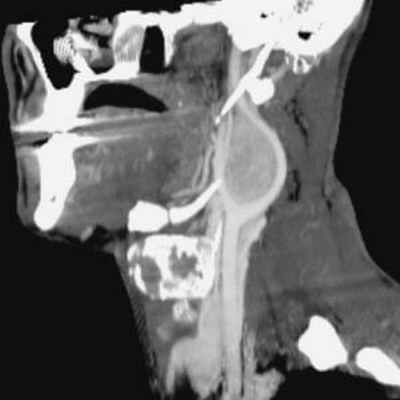

Если эндоскопия носа показала изменения в носоглотки , то тесты могут включать КТ или МРТ, и биопсию тонкой иглой этого поражения.

КТ лицевого отдела черепа, шеи и грудной клетки является необходимым. Если первичная опухоль не найдена, она должна быть проведена тонкая аспирационная биопсия массы.

Диагностировать новообразование, даже при отсутствии симптомов и болевых ощущений, можно при помощи МРТ мягких тканей шейного отдела. Обследование позволит выявить образование, определить размеры, а также связь с другими сосудами, тканями и органами.

Попадая на прием к врачу, пациент изначально проходит визуальный осмотр, после которого врач установит точный диагноз и назначит лечение. Для определения полной клинической картины вас направят на дополнительные обследования (компьютерная и магнитно-резонансная томография, УЗИ, анализы крови и др.).

Компьютерная томография (КТ) и магнитно-резонансная томография (МРТ) эффективны при постановке диагноза. Эти методы также помогают определить размер опухоли и идентифицировать любые другие опухоли в области шеи. Достаточно часто, знания из области ангиографии (наука, изучающая работу кровеносных сосудов шеи) применяются для выявления кровоснабжения опухоли, а также для определения способов его циркуляции в мозг. В большинстве случаев, биопсия опухоли не производится до начала лечения, так как она может вызвать обильное кровотечение.